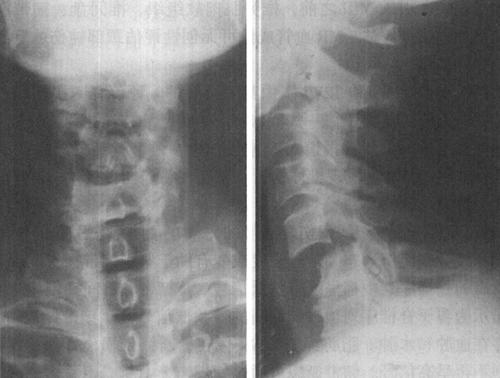

(一)X线平片和X线体层摄影

X线平片是脊柱损伤后的最基本和最重要的影像学检查方法,主要观察脊柱骨折和脱位情况。X线平片具有简单、易行和快速等优点,且可在不搬动疑似急性脊髓损伤患者的情况下在床边拍摄。X线平片空间分辨率高,骨骼结构成像清晰,目前仍是脊柱脊髓损伤检查的首选的影像学检查方法(图7-1)。临床上绝大多数的脊柱创伤骨折、关节脱位和半脱位都可通过普通X线的适当体位的投照而发现(图7-2)。脊柱常规投照位置有前后位、侧位和左、右斜位等。高质量的照片是诊断的最基本条件,如果一次照片不能满足诊断的需要,应调整相应的投照条件、胶片位置、球管中心以及投照角度重复拍摄,直至满意为止。对于怀疑有脊柱脊髓损伤患者应该在尽可能少搬动患者的情况下进行X线照片,尽量避免由于搬动病人而造成脊髓损伤加重。由于X线平片是投照部位解剖结构的重叠图像,限制了对复杂骨结构,特别是中轴骨骼解剖细节的显示,易漏诊细微而重要的骨折和错位。

图7-1 正常颈椎X线侧位片:正常颈椎前、中、后三柱连线光滑连续,中、后柱连线之间为脊髓所在

图7-2 C5以上前脱位,中、后柱连线显示在C5水平处明显狭窄,表明颈髓在此处受压